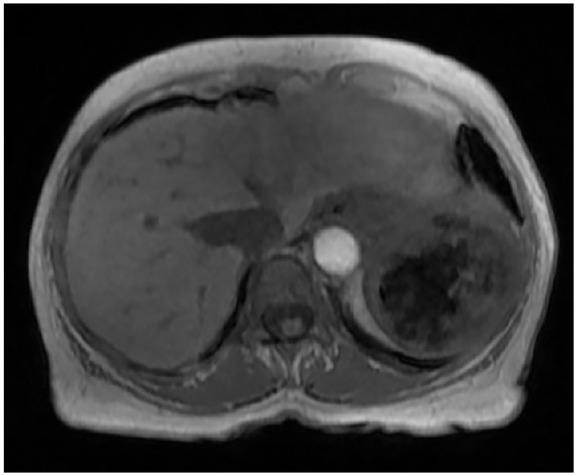

Littoral cell angioma (LCA) is a rare primary splenic vascular neoplasm originating from the littoral cells of the reticuloendothelial system. Splenectomy is the accepted mode of definitive diagnosis and treatment. With fewer than 200 reported cases, LCA remains poorly understood. Herein, we provide an enhanced insight into its histology and highlight the role of nuclear imaging in aiding LCA diagnosis. A 63-year-old female with a history of stage II multiple myeloma (MM) and rheumatoid arthritis was incidentally found to have a slowly enlarging splenic mass over a 6-year period. Given her candidacy for autologous hematopoietic stem cell transplantation for MM, further evaluation of the splenic lesion was pursued using nuclear medicine (NM) liver-spleen scan, which revealed a photopenic region consistent with a benign hemorrhagic mass. Subsequent splenectomy and histopathological analysis confirmed the diagnosis of LCA, with immunohistochemistry demonstrating CD68+ and CD31+ expression, highlighting LCA's unique dual histiocytic and endothelial character. This case highlights the diagnostic challenge posed by LCA due to its nonspecific clinical presentation and imaging findings. While splenectomy remains the gold standard for diagnosis, our findings suggest that NM liver-spleen scan imaging may aid in differentiating LCA from malignant splenic masses preoperatively. Furthermore, this case reinforces the association between LCA and hematologic malignancies, supporting the hypothesis that immune dysregulation may play a role in its pathogenesis. This underscores the importance of considering LCA in the differential diagnosis of splenic masses, particularly in cases involving a history of malignancy and/or immune system abnormalities.